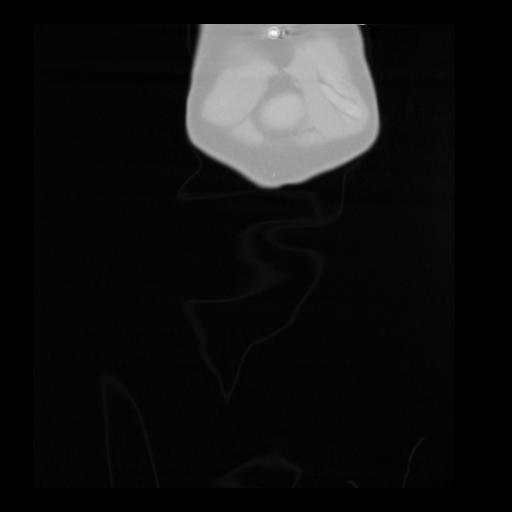

35 CUERPO,CE,Coronal,3.000,CUERPO,Coronal,